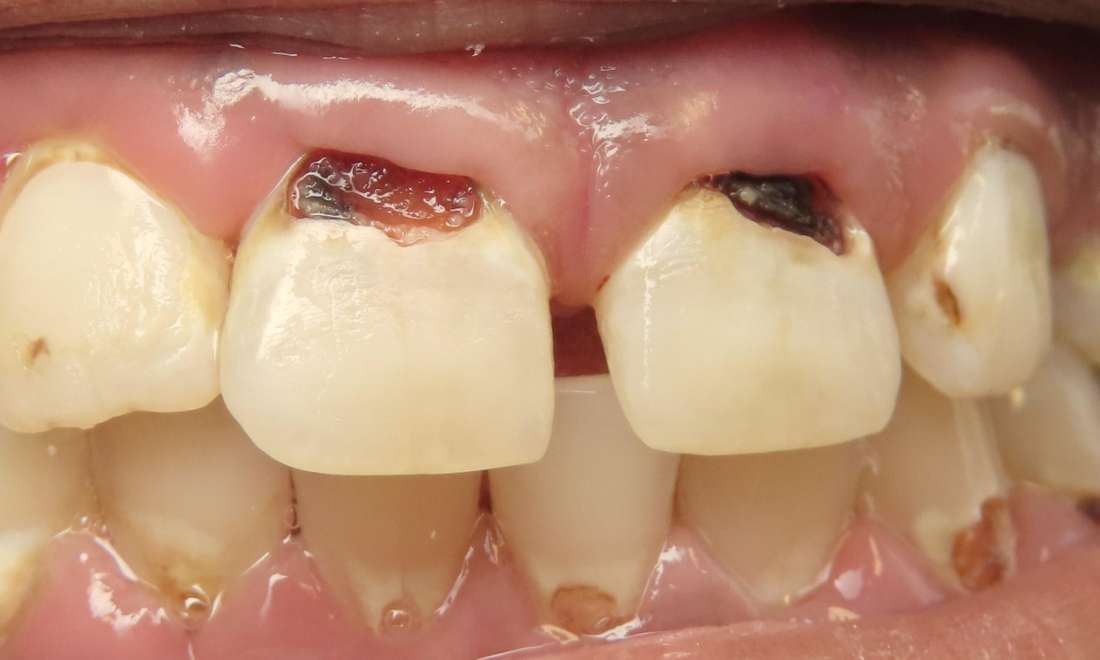

Transforming chipped, uneven, or discolored front teeth has never been easier with anterior composite bonding. This patient had very unsightly cavities on both front teeth. Within about an hour, the cavities were cleaned out and composites were placed. She was so happy with the result. This quick, minimally invasive procedure can give your smile a natural, refreshed look in just one visit.